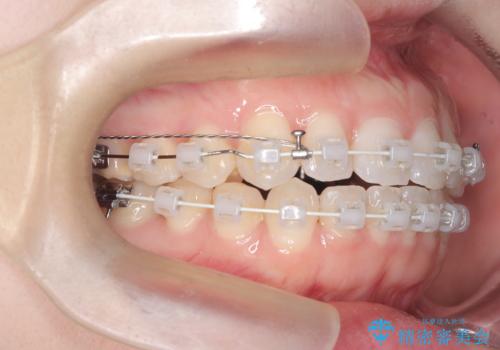

- 右上の八重歯と歯並びのデコボコを気にされて来院されました。精密な検査の結果、歯列のスペースがわずかに不足していることが判明。患者様の「抜歯を避けたい」というご希望を最大限に尊重し、アンカースクリュー(TAD)を用いて奥歯(臼歯部)全体を後方へ移動させることで、八重歯が並ぶスペースを確保する治療計画を立案しました。装置にはワイヤー矯正を使用し、確実で効率的な歯の移動を目指します。

今回のワイヤー矯正治療では、抜歯せずに歯を並べるスペースを作るため、特殊な小さなインプラントであるアンカースクリュー(TAD)を一時的に使用しました。このアンカースクリューを固定源として、奥歯(臼歯部)全体を後方へ遠心移動させました。従来の矯正では難しかったこの奥歯の移動を確実に行うことで、前歯の八重歯を適切な位置に並べるスペースを確保。治療の結果、抜歯することなく右上の八重歯と叢生が解消され、機能的にも審美的にも整った美しい歯並びを獲得していただけました。